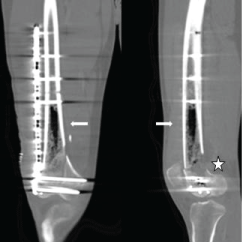

However, given the concern of the medical team due to the possibility of the existence of another infectious focus at the level of the fracture concomitant to the urine infection, a second CT scan of the knee was performed (Figure 2). We objectified the presence of an important amount of intramedullary gas. This was discussed with the Infectious Diseases Unit considering the possibility that the gas was secondary to an infection. Nevertheless, given the good clinical evolution and once the UTI (Urinary Tract Infection) was treated, the proper postoperative local evolution, the absence of collections in CT scan, and the unique finding of gas in the thigh (which, in turn, didn’t seem to be related with the isolated germ, as the enterococcus is not a gas producer), we decided to perform watchful waiting under active clinical-analytical surveillance, removing all antibiotic therapy after 12 days.

Figure 2: Last CT in coronal (left image) and sagittal (right image) planes with bone windowing, at the same level than Figure 1. A wide presence of air into the medullary canal of the right femoral diaphysis can be depicted (arrows). A posterior cortical defect is shown (next to the star). View Figure 2

Given the good clinical, functional and analytical evolution of the patient, we considered that the finding of gas in the CT scan performed after the debridement by enterococcus was a "casual" finding not related to the germ that produced the infection, which may be a result of cleansing with a pressure gun. The evolution was favorable, with an articular balance of flexo-extension 20°-0° during the immediate postoperative, without repeating fever episodes and keeping a good appearance of the wounds. After a year of follow-up, the articular balance is of 70°-0°, without pain, and with an autonomous gait without assistance.

In Luey, et al. [5], it is stated that the presence of endomedullary gas in the axial skeleton is pathognomonic for emphysematous osteomyelitis. However, in our case, the existence of intramedullary gas was not secondary to an infection or pneumocysts. The CT scan performed before the definitive surgery didn’t show any intra-articular or interosseous collection, neither gas inside the joints or the surrounding tissues, after having performed a manual cleaning with saline irrigation. Following the pulsatile debridement with a pressure gun that was required after an infection by E. faecalis (the only time when pressure cleaning was performed) we did a new CT scan in which we could observe gas inside the joint and the medullary canal. There was no evidence of radiological signs of osteomyelitis and, given the absence of clinical symptoms characteristic to this pathology, the absence of gas production by E. faecalis, and the support of complementary tests, the presence of intramedullary gas could be attributed to the use of irrigation with a pressure gun.

In the case presented here, and as seen in the picture Figure 2, his femur presented a posterior metaphyseal cortical defect that could favor the entrance and spread of air through the diaphyseal canal. We can conclude that, in the presence of intramedullary gas in imaging tests as the only finding, without clinical and analytical alterations which could suggest an infection, the use of a pressure gun for a pulsatile intrasurgical cleaning must be considered as a possible mechanism responsible for the existence of air at the level of soft tissues and inside the medullary canal. Of course this conclusion should be made after discarding most common causes of intramedullary bone gas, besides infection, like penetrating trauma, pneumocysts or emphysematous osteomyelitis.